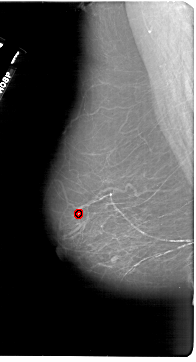

A_1849_1.LEFT_MLO

FILE: A_1849_1.LEFT_MLO.OVERLAY

TOTAL_ABNORMALITIES 1

ABNORMALITY 1

LESION_TYPE MASS SHAPE OVAL MARGINS CIRCUMSCRIBED

ASSESSMENT 4

SUBTLETY 3

PATHOLOGY MALIGNANT

TOTAL_OUTLINES 1

BOUNDARY